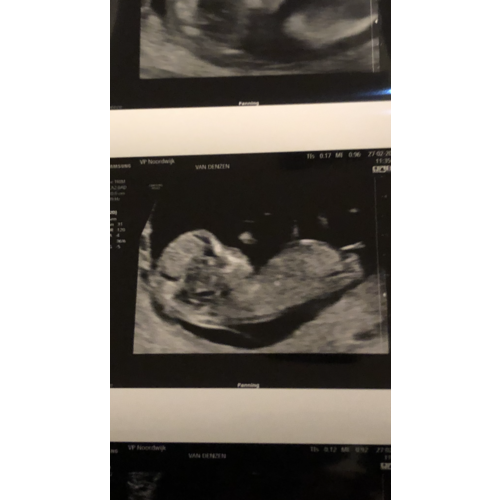

Moeilijk te zien.. maar hebben jullie een idee misschien? Nog 8 dagen.. dan ...

De nub is goed verborgen achter het beentje maar ik gok op boy 💙